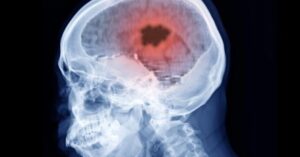

Mrtvice

Výzkumný tým vedený Dr. Nadií McMillan z nemocnice Lahey Hospital & Medical Center v Massachusetts publikoval v časopise The Neurohospitalist neobvyklý případ : U 30leté ženy se do tří týdnů...

Když oběti mrtvice vykazují špičaté proteiny v mozkových tepnách i více než rok a půl po obdržení experimentálních výstřelů mRNA,...

Nová vědecká studie zjistila, že mRNA „vakcíny“ proti Covid-19 po spuštění očkovací kampaně jsou spojeny s ohromujícím 1100násobným nárůstem výskytu...

Podle studie Dr. Podle Petera McCullougha a kolegů měly vakcíny COVID-19 více než 1000krát zvýšené riziko vzniku krevních sraženin v...

Několik studií naznačuje zvýšené riziko mrtvice při současném podávání vakcín proti Covidu a chřipce. Důvodem je zjevně zvýšená tvorba krevních sraženin...